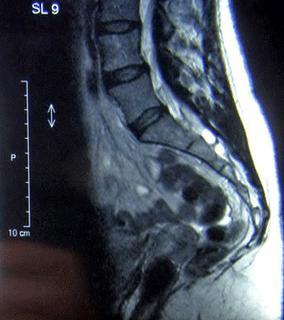

Por lo general son asintomáticos y suelen diagnosticarse de forma incidental al realizar una resonancia magnética (RMN) por otra causa, pero en raras ocasiones los quistes pueden comprimir las raíces nerviosas adyacentes y generar dolor lumbosacro, ciática, coccigodinia (dolor localizado en el coxis debido a una neuralgia de los nervios sacros o a una lesión en el coxis) y síntomas y signos neurológicos de diversa severidad, maniobra de Lassègue positiva (maniobra que denota afectación del nervio ciático) e, incluso, trastornos motores y sensitivos.

El diagnóstico diferencial debe hacerse con las herniaciones de los discos intervertebrales y se realiza a través de la melografía. También son útiles para el diagnóstico el escáner y la resonancia magnética, confirmándose mediante la saculoradiculografía.